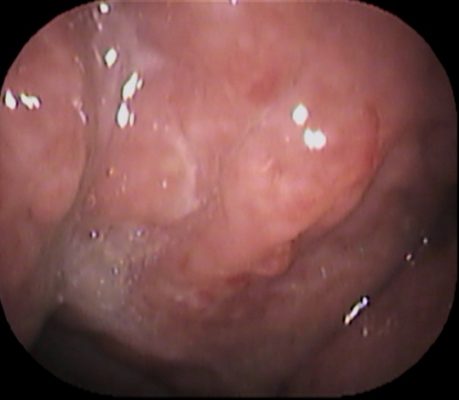

ファイバーで上咽頭をチェックしてみます。

![phr-ne11[1]](https://www.inoue-ent-cl.jp/webcms/wp-content/uploads/2024/12/phr-ne111.jpg)

上咽頭 とはここです↓

上咽頭は、軟らかく出血しやすい粘膜に見えました。

この所見から 慢性上咽頭炎と診断。患者さんと相談し、Bスポット治療を開始してみます。